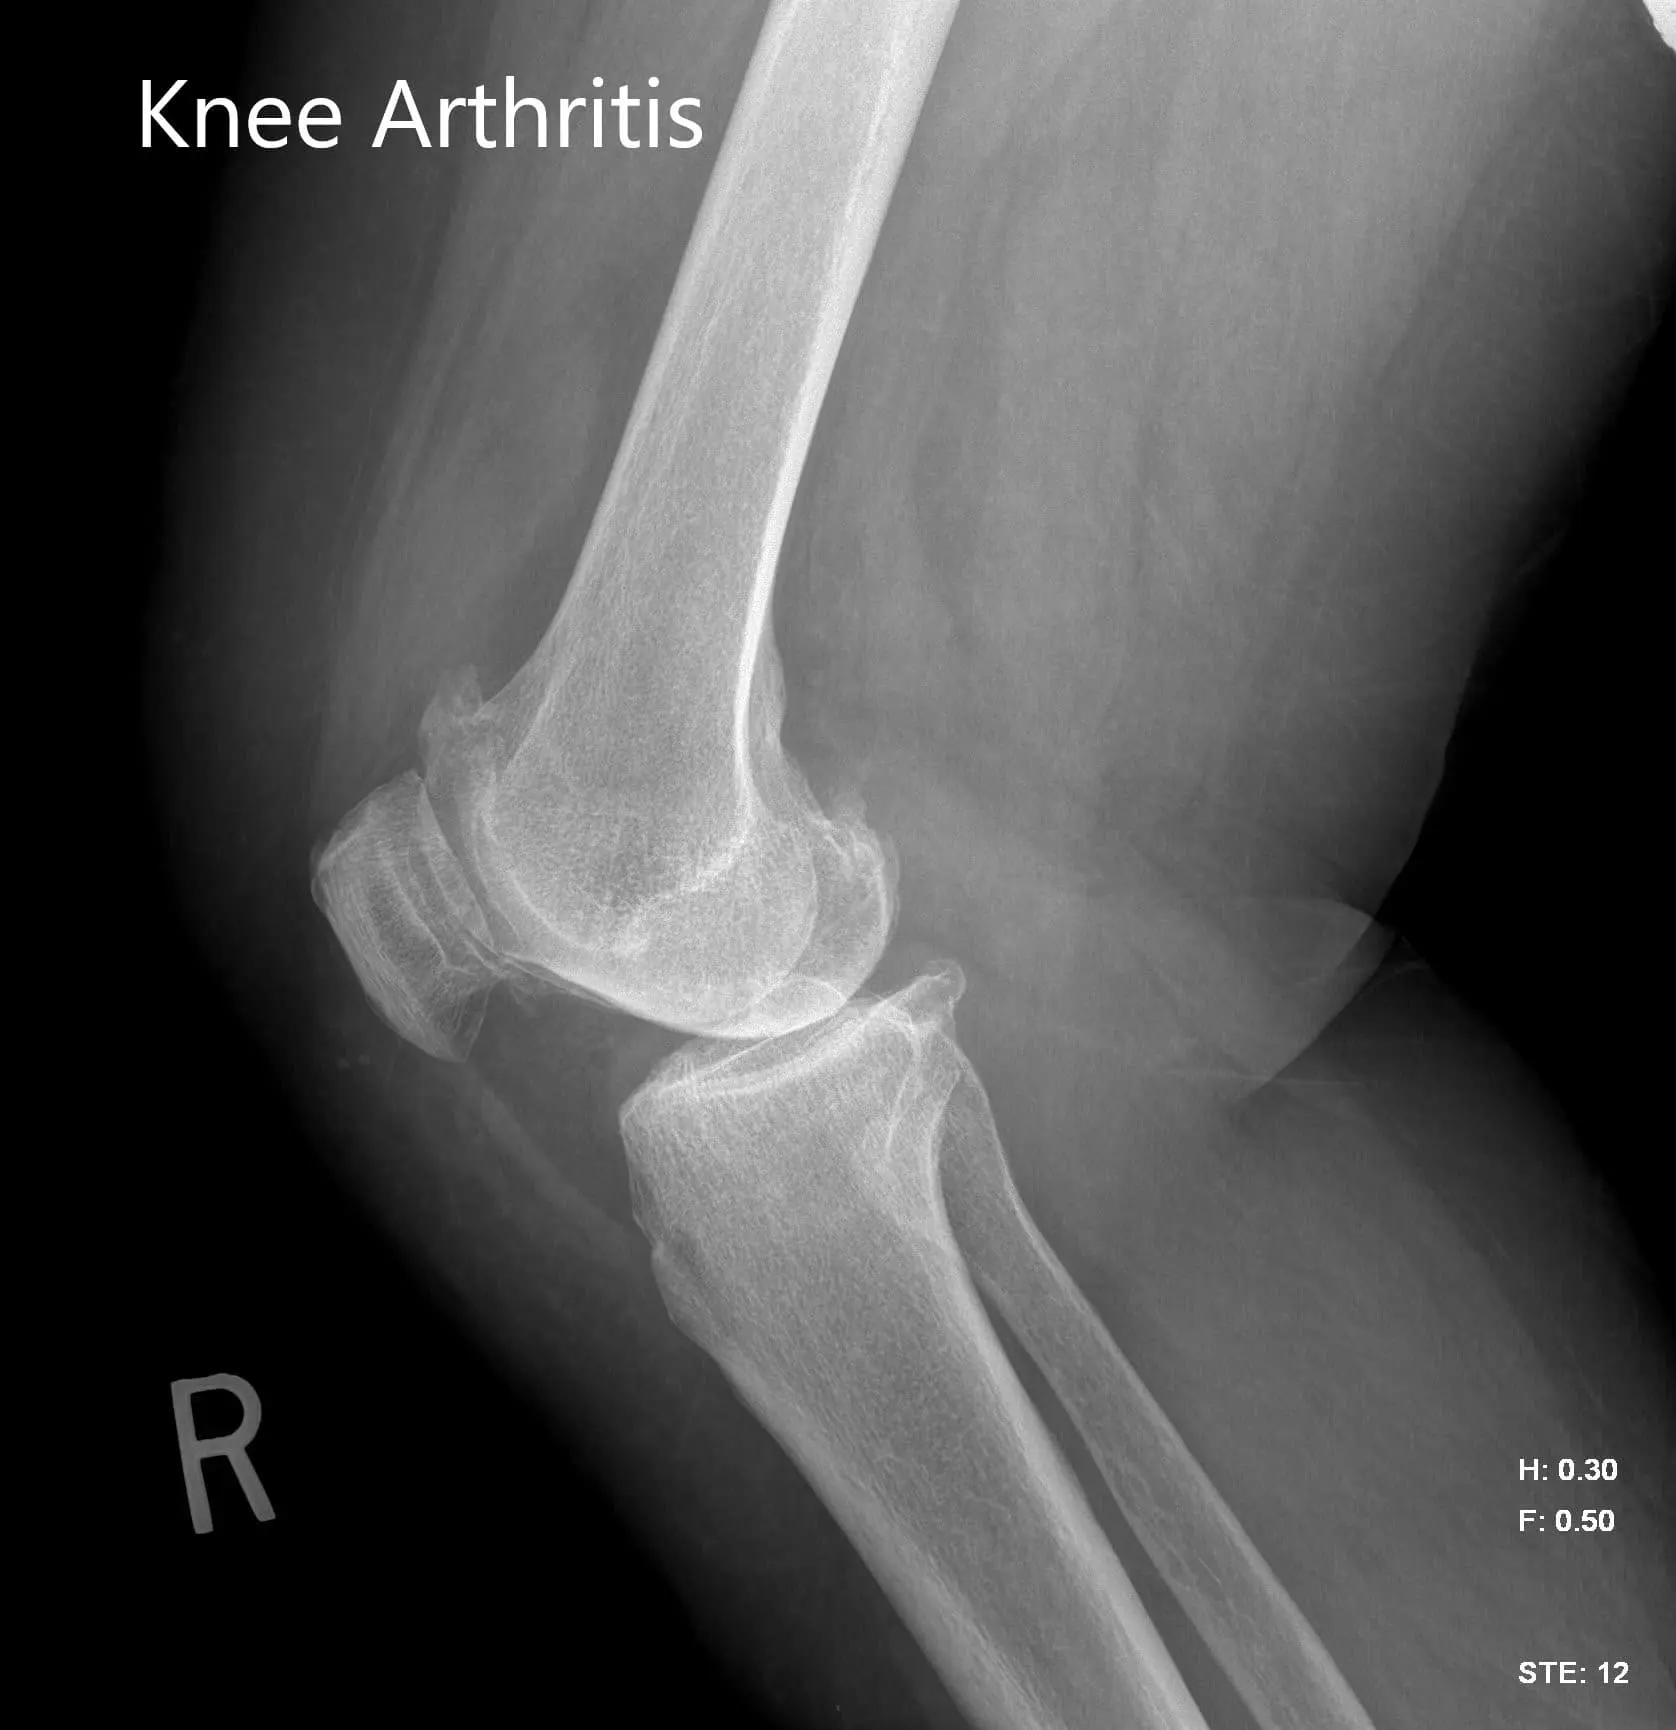

Imaging studies were obtained revealing tricompartmental osteoarthritis of the right knee with severe involvement of the medial compartment. Considering the patient’s condition and demands, he was deemed as a candidate for total knee replacement with custom implants. Other treatment options including nonsurgical methods were discussed in detail with him. He agreed for a custom right knee replacement.

Preoperative X-ray image of the right knee showing AP and lateral views